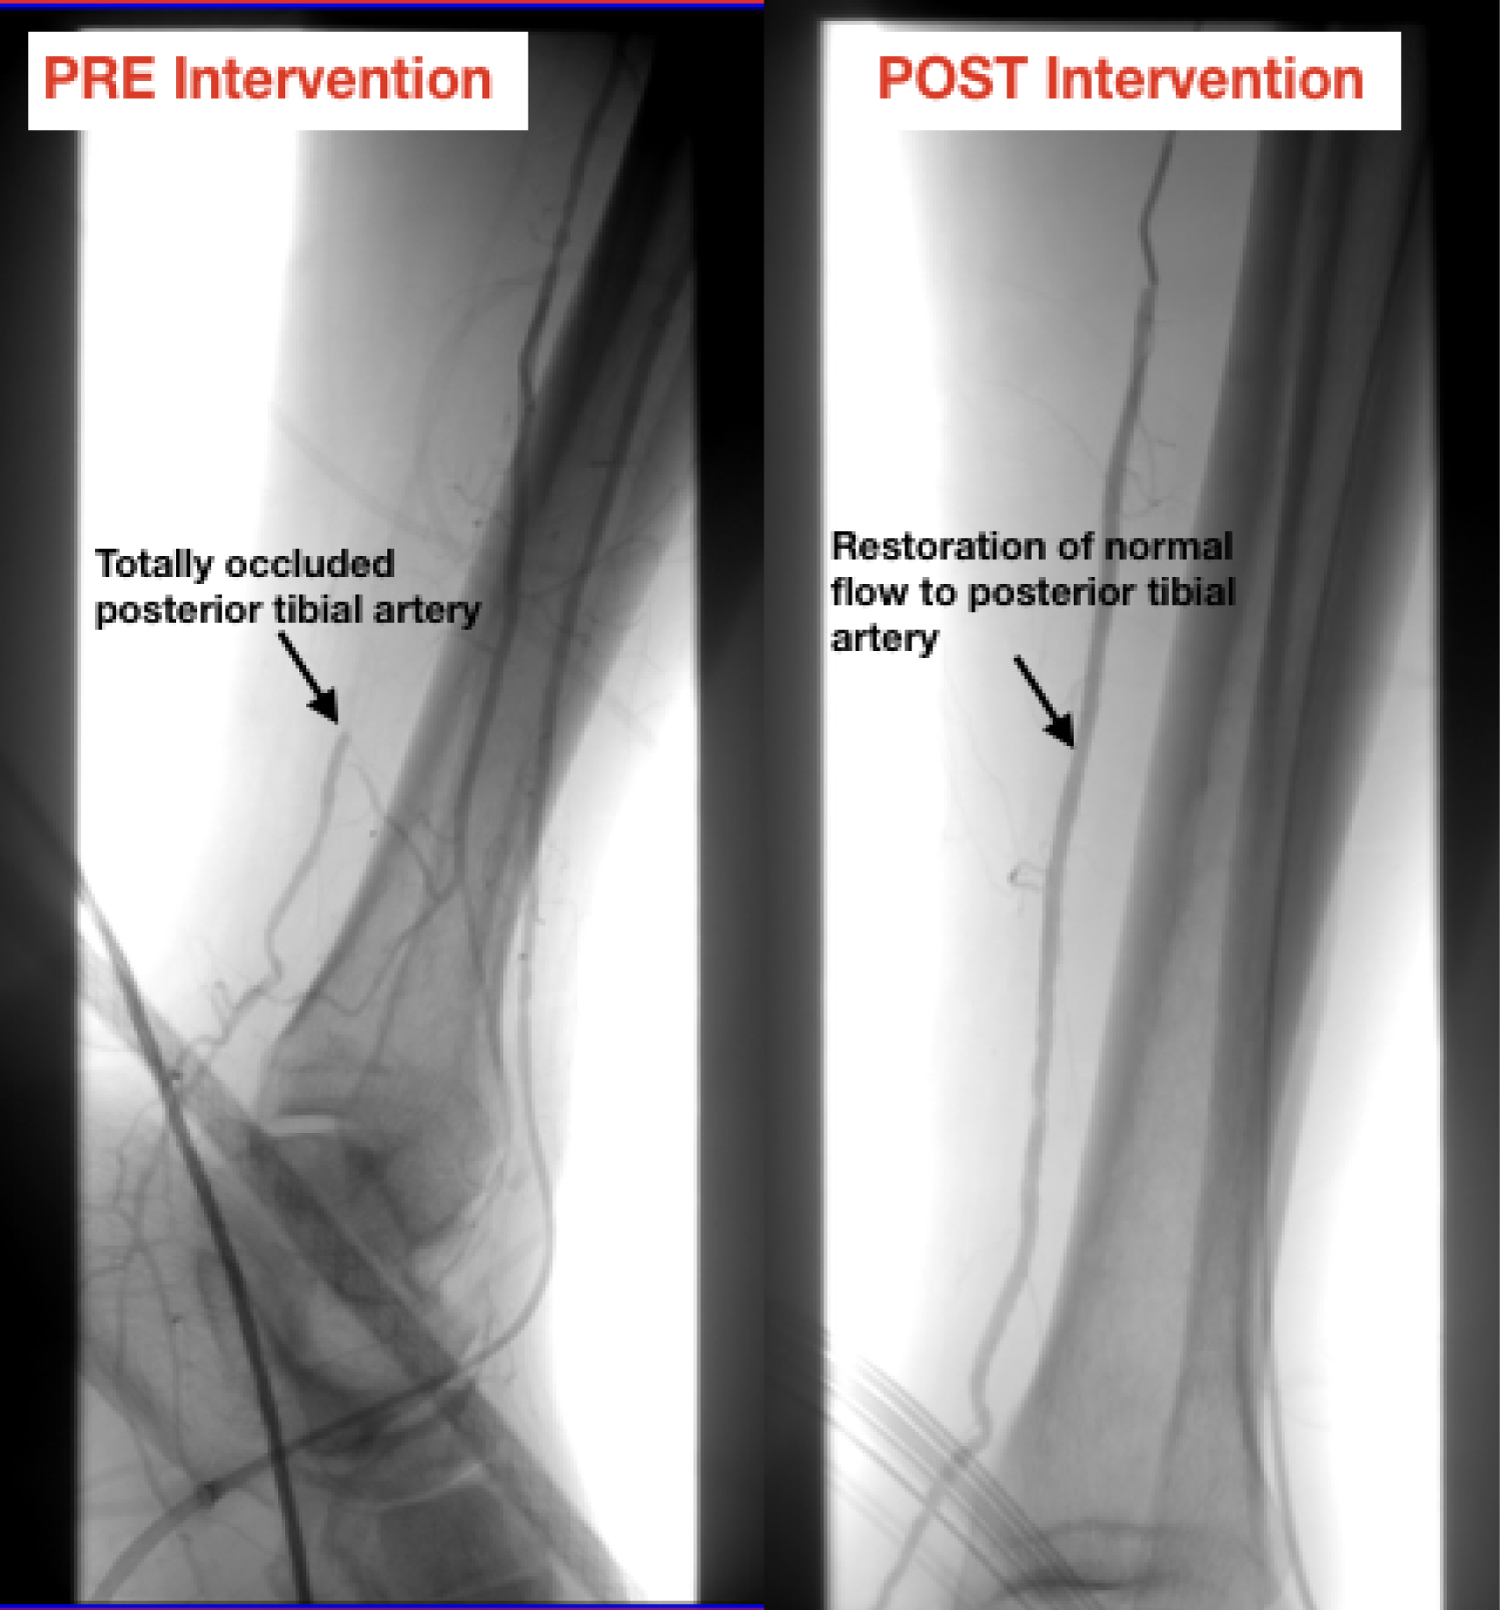

Given the extensive PAD history, there was high suspicion for acute limb ischemia (ALI Stage IIb) and the vascular team was consulted, and an urgent angiogram was planned. The team faced a challenge in choosing an adequate vascular access site in a patient with an extensive surgical bypass history in both his lower and upper extremities. Both contralateral femoral and ipsilateral anterograde femoral accesses were not an option. Therefore, a retrograde ipsilateral transpedal approach was chosen as it was the only remaining option. Ultrasound-guided access of the anterior tibial (AT) artery was performed and a 4Fr Pinnacle precision sheath (Terumo) was placed. Subsequent angiography through a Vertebral catheter (Cordis) revealed a patent fem-fem bypass, chronic total occlusion of the left iliac artery, patent superficial femoral artery (SFA) and popliteal arteries and total occlusion in the left posterior tibial (PT) artery with a reduced flow into the foot and likely the embolic culprit to the patient's acute symptoms (Figure 2).

Figure 2: Pre- and post-intervention angiogram. Arrow points to posterior tibial artery, highlighting restoration of normal flow after intervention. View Figure 2